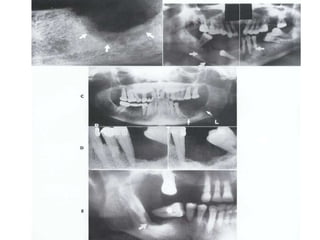

Mixed form of ostiosarcoma: In addition to areas of

new bone formation, osteolysis and

destruction of the compact bone can be

observed. Note the areas of spicules

(arrows)

Sarcoma

This tumor, which affects males twice as

females, exhibit a predilection for the

mandible.

Radiographically, bone destruction as well as

new bone formation and osteolysis can be

observed, along with perforation of the

compact bone with spicules (sunrays

effect), where the lesion borders on the

soft tissues